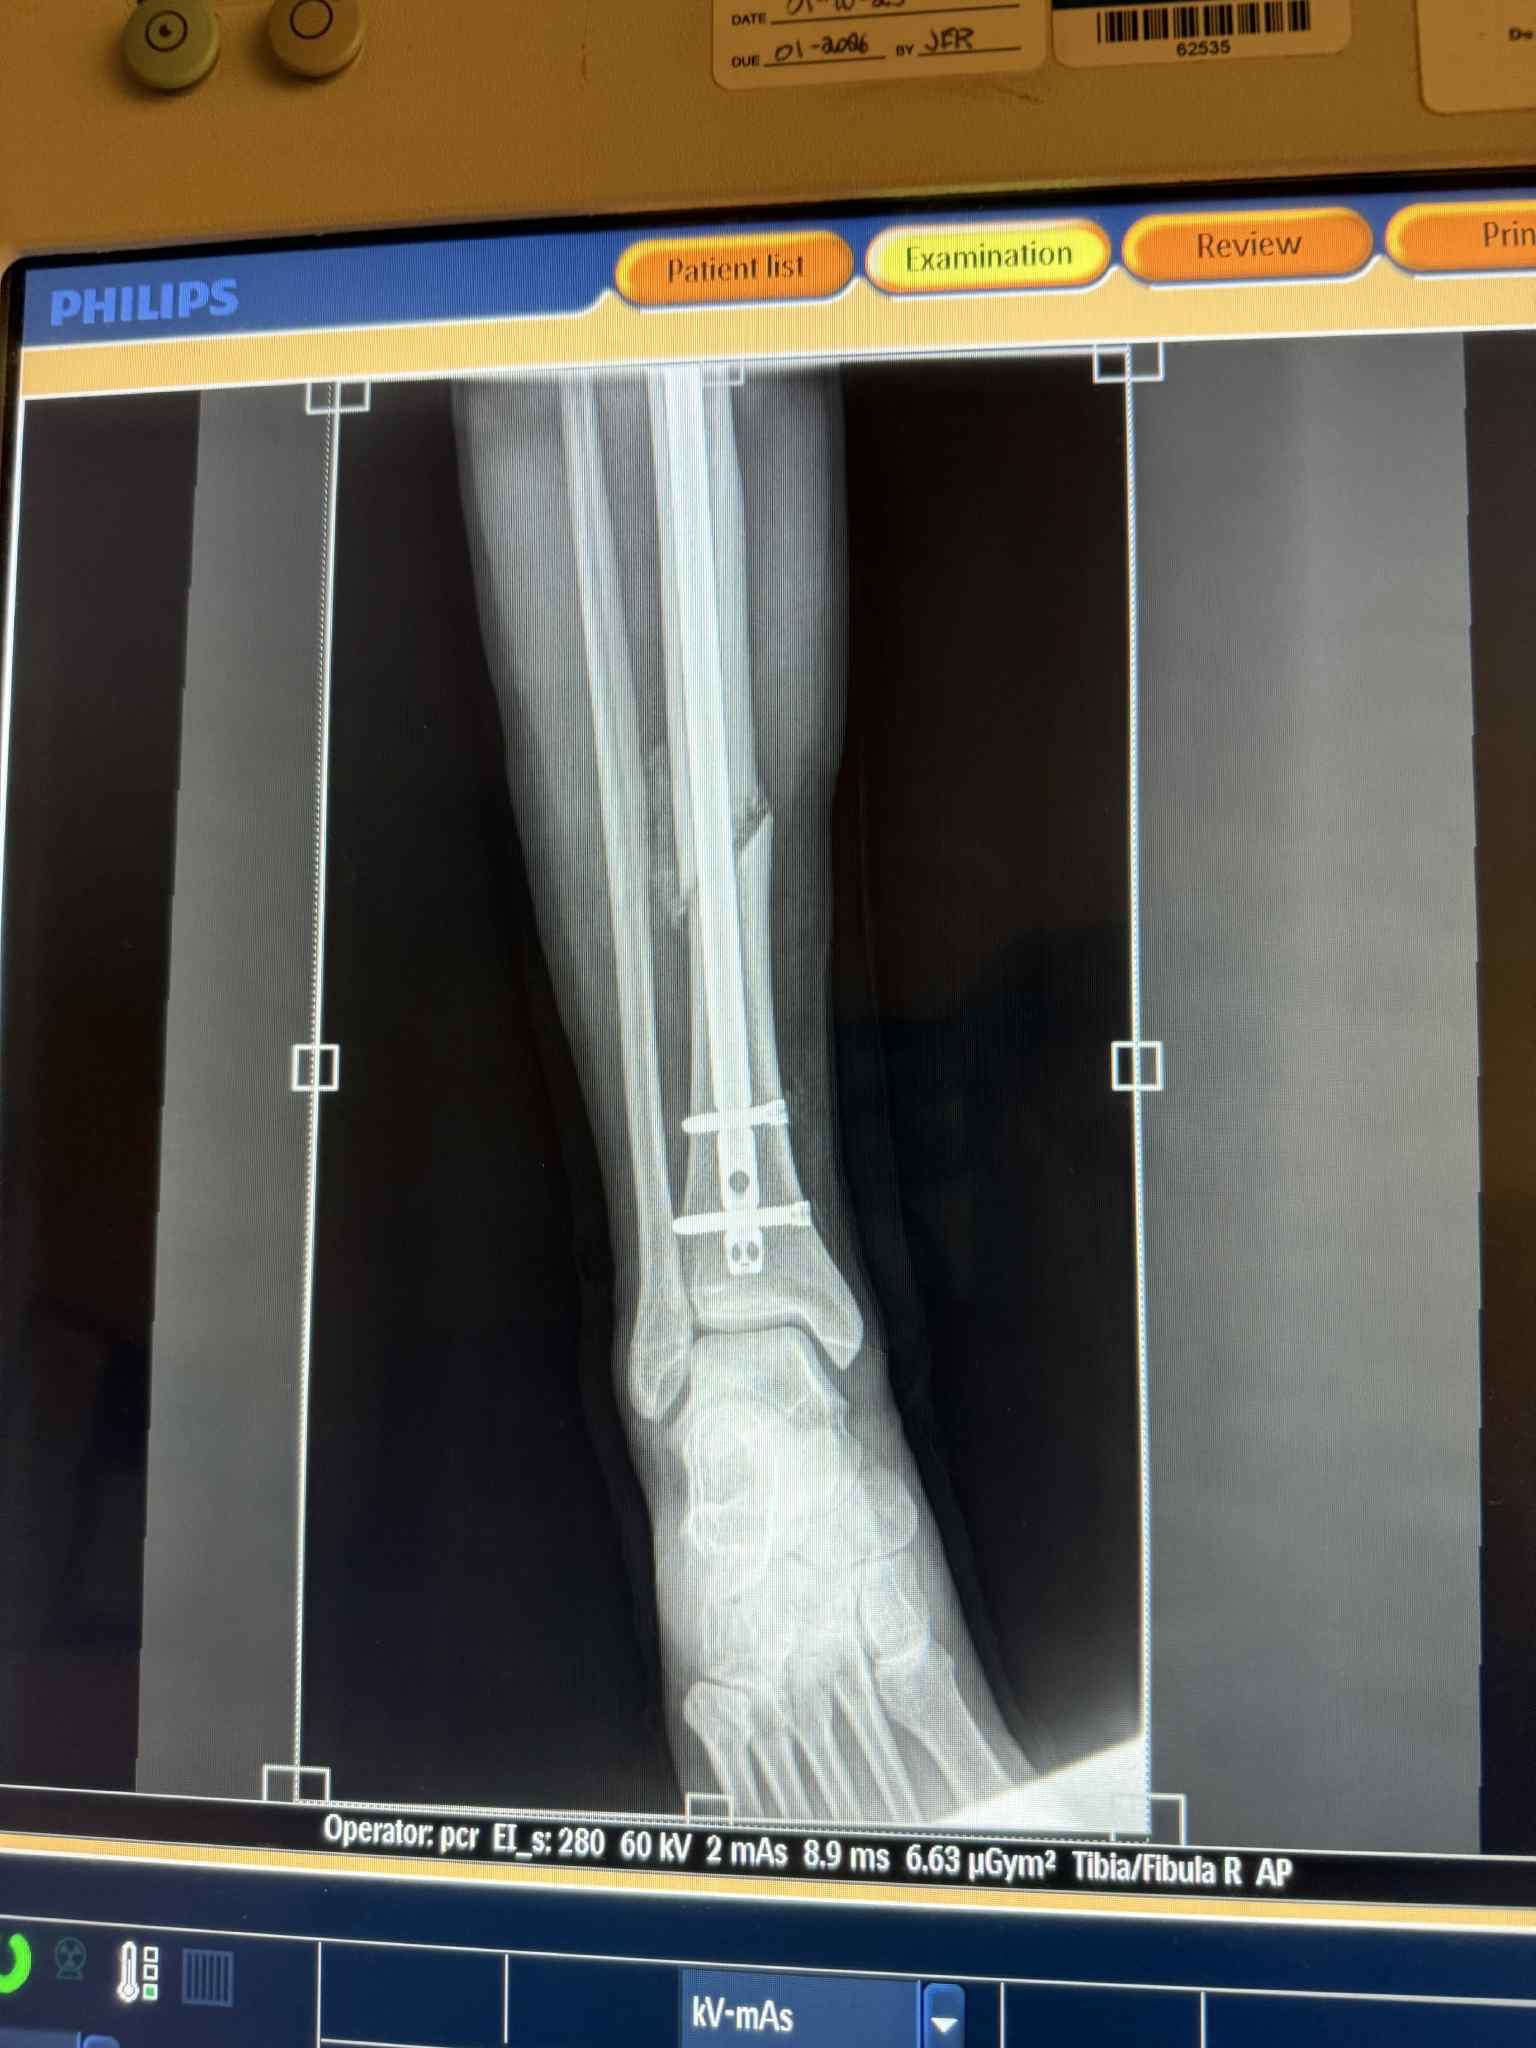

Sara Del Fabrro is an Italian apprentice jockey who was having a successful summer meet at Delaware Park Racetrack until she was badly injured when a horse flipped over on her during morning training and broke her leg. She will be out 6-8 months.